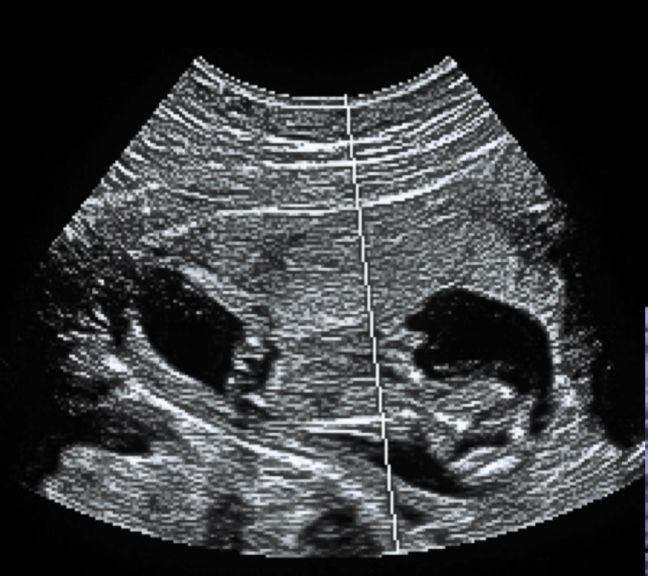

Interested in learning more about POCUS GYN Scanning Techniques?

Check out our other POCUS lectures: - POCUS Basics: Identification of an IUD - POCUS Basics: Intrauterine Pregnancy and Early Pregnancy Loss - POCUS Basics: Ectopic Pregnancy